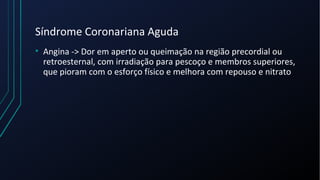

Dor torácica pode ter diversas causas, incluindo cardíacas como síndrome coronariana aguda, dissecção de aorta e pericardite, e não cardíacas como problemas pulmonares, musculoesqueléticos e do trato gastrointestinal. É importante avaliar a história clínica, características da dor e exame físico para identificar a possível causa e orientar o tratamento adequado.